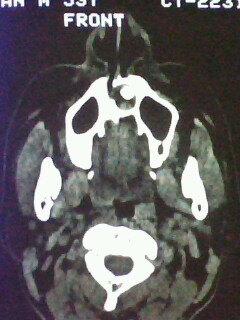

以下是引用随光逐影在2009-5-20 19:22:00的发言:[br]1)考虑左上颌骨近中线区含牙囊肿。2)鼻中隔右突偏曲。3)双侧下鼻甲肥大。